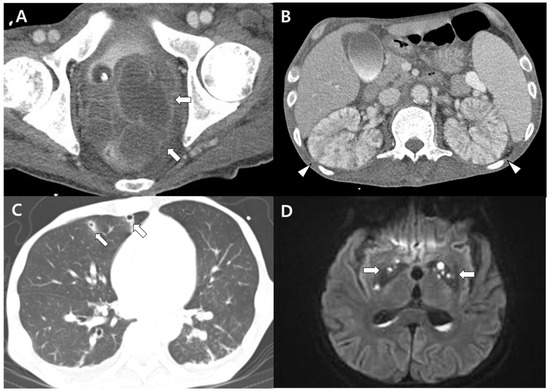

Invasive Hypervirulent Klebsiella pneumoniae Syndrome Originating from an Anorectal Abscess as Opposed to a Pyogenic Liver Abscess

An immunocompetent 49-year-old man presented with swelling and pain in the lower region of his left leg that had lasted for 4 weeks. The diagnosis was severe pyomyositis and osteomyelitis in the lower left leg caused by hypervirulent Klebsiella pneumoniae (hvKP) along with [...] Read more.

An immunocompetent 49-year-old man presented with swelling and pain in the lower region of his left leg that had lasted for 4 weeks. The diagnosis was severe pyomyositis and osteomyelitis in the lower left leg caused by hypervirulent Klebsiella pneumoniae (hvKP) along with multiple metastatic infections in the kidneys, lungs, and brain originating from an anorectal abscess. A virulence-gene analysis revealed that the isolated K. pneumoniae harbored rmpA, entB, ybtS, kfu, iutA, mrkD, and allS-virulence genes and belonged to the K1 capsular serotype. After repeated abscess drainage procedures, intravenous ceftriaxone was administered for more than 10 weeks, and the patient’s infection was controlled. We focused on the clinical features of hvKP originating from an anorectal abscess without a pyogenic liver abscess. We suggest that hvKP be considered a causative pathogen of pyomyositis and osteomyelitis resulting in multiple metastatic infections in an immunocompetent patient, and more information on the unexpected multiple metastatic infections should be obtained from a virulence analysis of K. pneumoniae. Full article